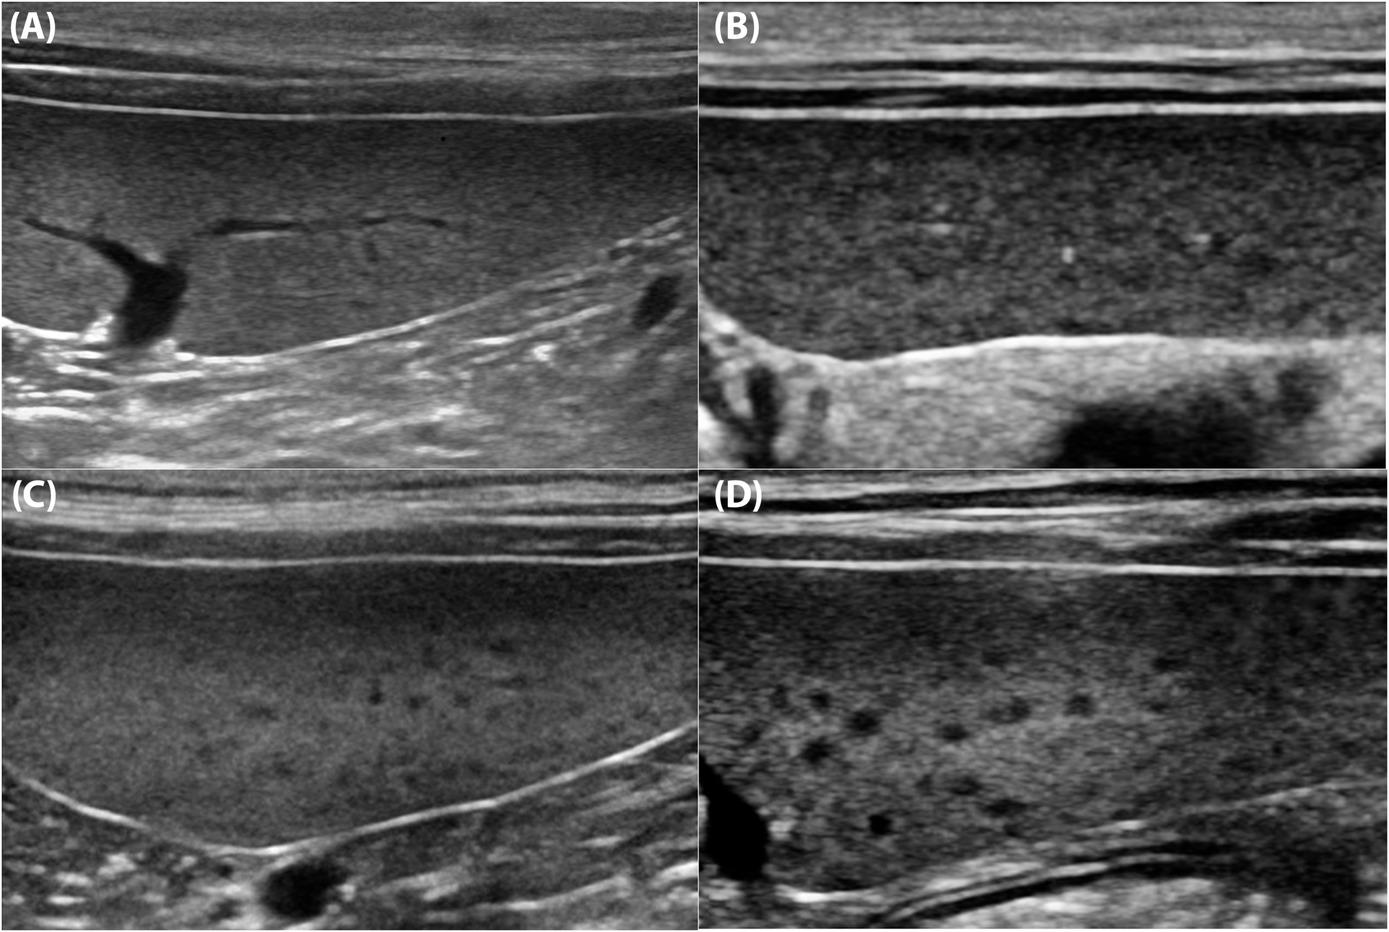

Autoři definovali 4 typy vzhledu sleziny, které jsou uvedeny na přiloženém obrázku.

Ve věku 4 týdny má slezina homogenní granulární vzor. Tento se postupně mění na retikulonodulární vzor se zvětšujícími se hypoechogenními uzlíky. 🌾

Nejvýraznější retikulonodulární vzor je mezi 28. a 36. týdnem věku psa. Uzlíky jsou větší a dobře ohraničené. 🧶

Kolem 60 týdnů věku vzhled postupně přechází zpět na homogenní granulární vzor. 🔄

Pozorované změny vzhledu jsou zřejmě součástí normálního vývoje lymfoidních folikulů ve slezině. 🔬